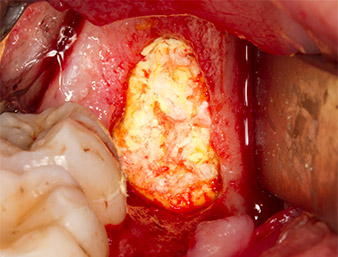

Frammenti ossei

Fig. 13: I frammenti ossei dall'area dell'intervento sono stati conservati in una soluzione salina sterile.

Successivamente, il tessuto osseo autogeno (Fig. 13) è stato posizionato nell'alveolo e nel circostante difetto osseo (Fig. 14). Un vello di collagene ricopriva i frammenti di osso fino a livello dell'osso come protezione per il nervo esposto (Fig. 15). Per chiudere il tessuto molle aperto sono state utilizzate suture con filo in Vicryl, USP 4.0 (Fig. 16). Dopo l'operazione sono stati prescritti una preparazione di Ibuprofene (Seractil 400 mg, 3x1) e un antibiotico costituito da amossicillina e acido clavulanico (Augmentin 1 g, 2x1).